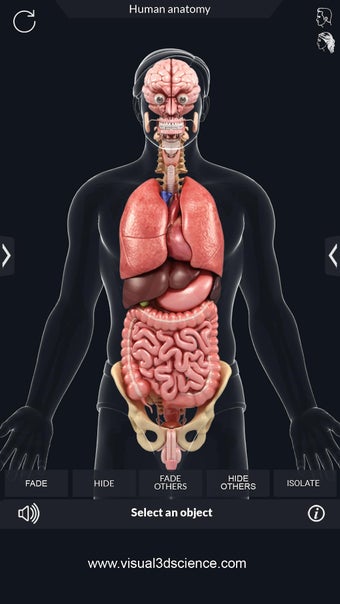

My Organs Anatomy es una aplicación de anatomía 3D gratuita desarrollada por Visual 3D Science para usuarios de Android. Esta aplicación proporciona un modelo 3D altamente realista de los órganos humanos que se puede girar 360°, acercar y alejar, y ver desde cualquier ángulo. La aplicación está diseñada para proporcionar una mirada detallada a la anatomía de los órganos humanos y ofrece varias características para ayudar a los usuarios a explorar y aprender.

La interfaz fácil de usar de My Organs Anatomy permite una navegación sencilla, lo que facilita la selección, rayos X, ocultación y visualización de órganos individuales. La aplicación también incluye un modo de animación, opciones de búsqueda y un panel de información que proporciona información relacionada. Además, la aplicación ofrece pronunciación de audio para todos los términos anatómicos, e incluso los usuarios pueden dibujar o escribir en la pantalla y compartir capturas de pantalla.

En general, My Organs Anatomy es una gran aplicación para estudiantes de medicina y cualquier persona que quiera explorar la anatomía de los órganos humanos en detalle. Con sus gráficos de alta calidad y numerosas características, esta aplicación proporciona una excelente experiencia de aprendizaje para los usuarios.